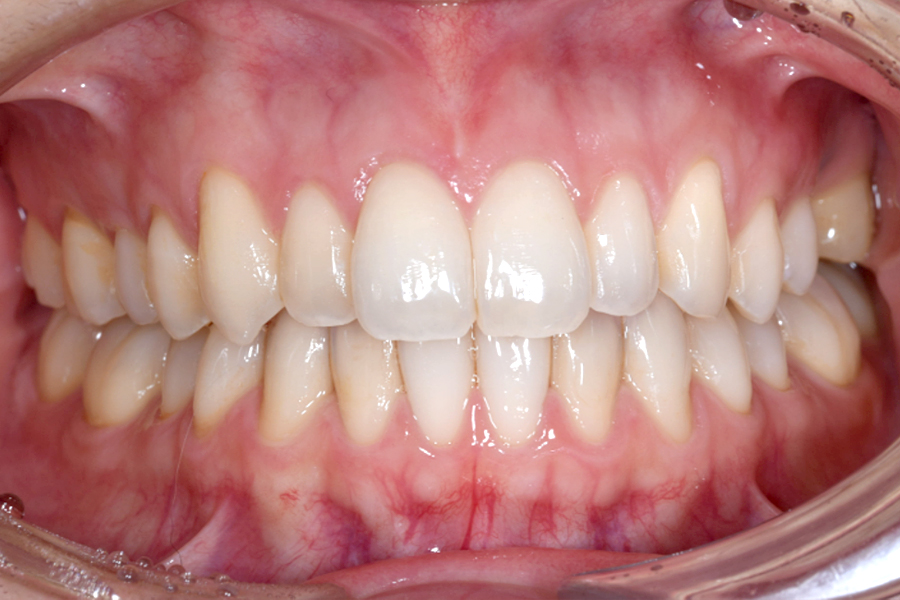

| 主訴 | 歯並びを治したい |

|---|---|

| 治療期間 | 5か月 |

| 治療費 | 部分マウスピース矯正(モニターキャンペーン)と ホワイトニングセット 422,596円(税込) |

| 治療内容 | 目立ちにくいマウスピース矯正 (非抜歯矯正) 歯と歯の間に隙間をつくることにより、歯列弓を広げながら治療を行いました。 また矯正用マウスピースをトレー代わりにし、ジェルを入れてホームホワイトニングを同時に行っております。 |

| 治療のリスク | ・後戻りする可能性があるのでリテーナーを最低でも矯正期間以上はつける必要があります。 ・ホワイトニング後、一時的に痛みが出る場合があります。 |